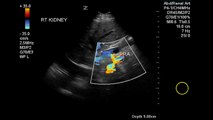

Color Doppler and pulsed Doppler demonstrate a stenotic portion of the renal artery. Parvus tardus is evident in Doppler wave=forms in the renal parechyma.\r